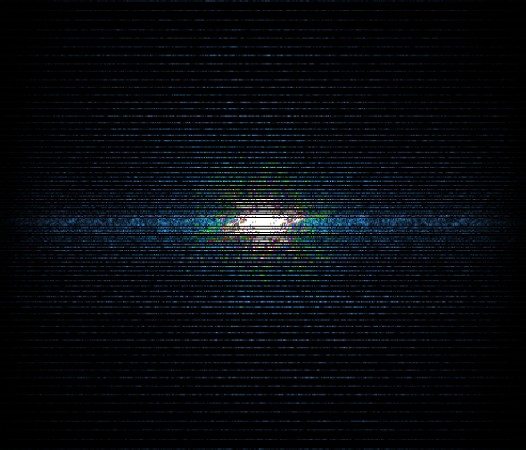

In the example below, only one fifth of the required MR radiofrequency signals is recorded. This results in a five times faster acquisition, with a subsampled k-space (top left) and inherent image artifacts after standard reconstruction (top right).

Basic compressed sensing principle